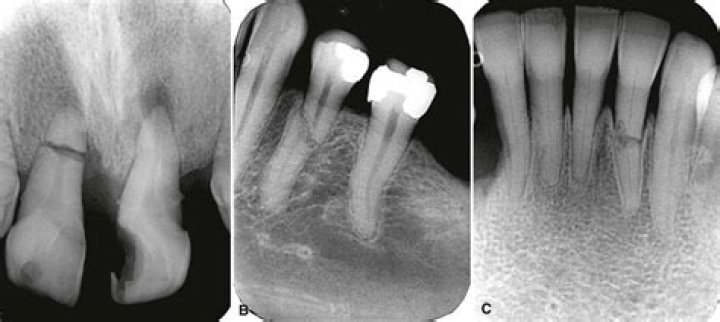

Does cracked tooth show up on xray?

X-rays usually do not show the small cracks that cause cracked tooth syndrome. Only if the cracks are wide enough, they may show up as shadows. Sometimes a special dye might be used to temporarily stain the tooth, and check to see if it is fractured.